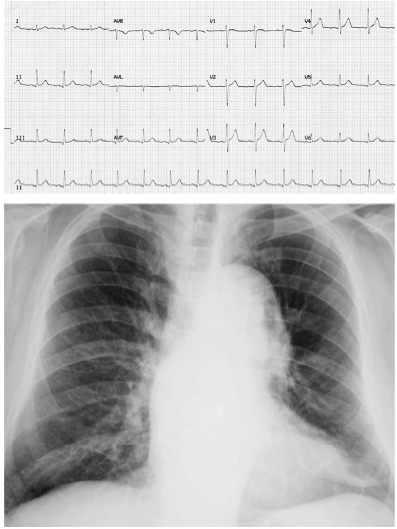

Um indivíduo de 32 anos de idade relatava dor torácica lancinante na parede anterior com irradiação para o dorso, de forte intensidade e sem alívio com analgésicos comuns havia seis horas. Ele possui antecedentes de subluxação do cristalino e ectasia dural lombosacral. Ao exame físico, encontrava-se sudorético e acianótico, com pressão arterial de 198 × 122 mm/Hg e frequência cardíaca de 92 bpm. Apresentava: pectus carinatum, ritmo cardíaco regular em dois tempos com sopro diastólico (++/4) no segundo espaço intercostal à direita, além de pulsos reduzidos em membros inferiores. O resultado da troponina ultrassensível e os exames laboratoriais de rotina foram normais. Realizou um eletrocardiograma e uma radiografia de tórax, que são mostrados a seguir.

Assinale a opção que corresponde a mais provável condição associada ao caso clínico apresentado no texto 18A03-III.